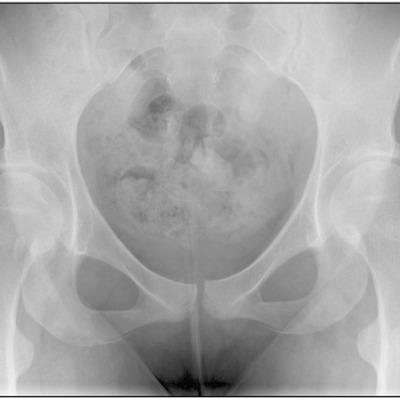

Click on an image below to view more info.